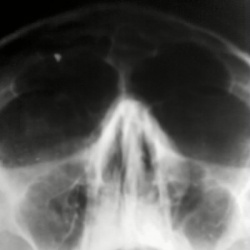

Уважаемые коллеги,как вы думаете есть ли отек справа в верхнечеллюстной пазухе?